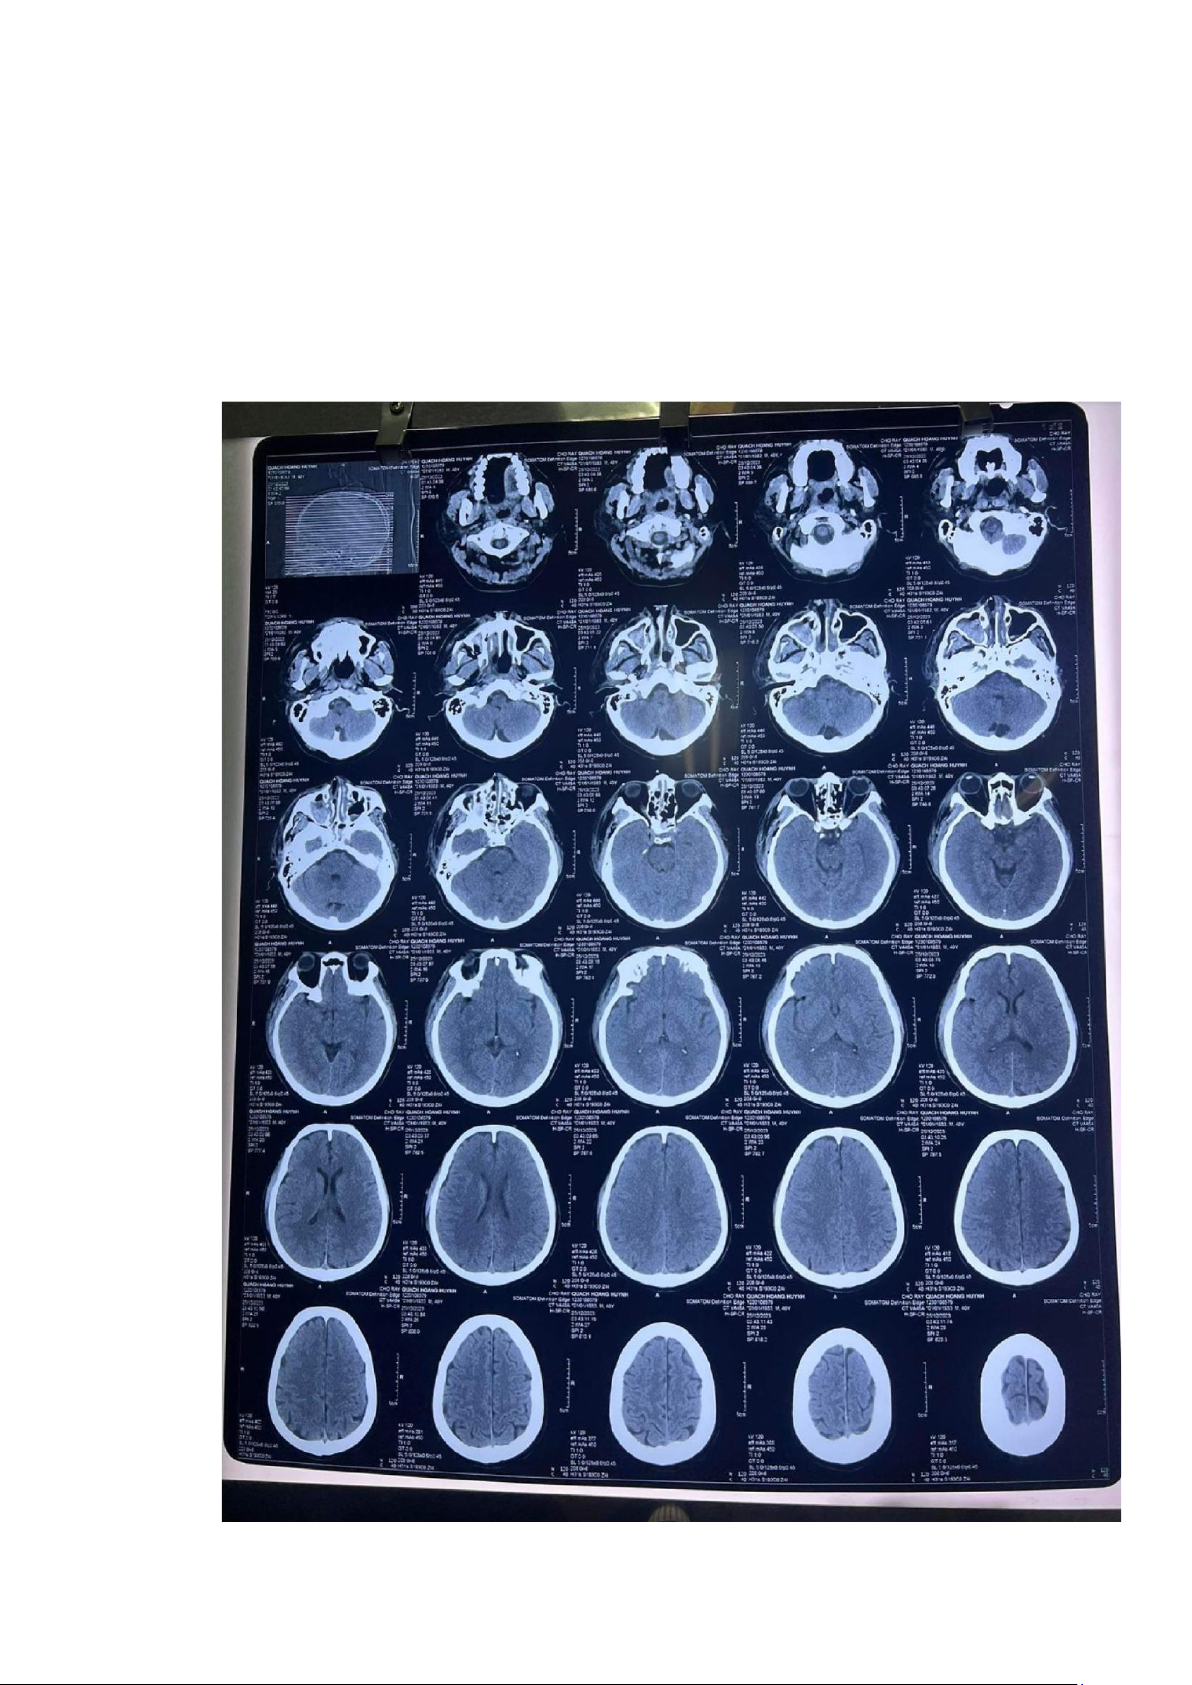

5. CTScan sọ não (25/12/2023 tại cấp cứu bv Chợ Rẫy):

• Không thấy máu tụ nội sọ

• Tụ khí nội sọ rải rác lOMoAR cPSD| 45469857

• Nứt sọ thái dương (P)

• Gãy xương hàm trên (P)

• Gãy thành ngoài hốc mắt, cung gò má, gãy thành xoang hàm (P), xoang bướm hai bên

• Tụ máu các xoang cạnh mũi

• Phù nề, tụ máu mô mềm hàm mặt, quanh mắt (P) lOMoAR cPSD| 45469857 lOMoAR cPSD| 45469857

Chụp lại CT scans sọ não 27/12/2023 (2 ngày sau chấn thương) Kết luận:

Tụ máu ngoài màng cứng vùng trán-đính (P)

Tụ máu dưới màng cứng lớp mỏng vùng trán (P) dọc lều tiểu não

Dập não xuất huyết trán (P), thái dương (P)

Xuất huyết dưới nhện rải rác bán cầu (P), não thất bên (P) bị chèn ép và di lệch đường giữa qua (T) nhẹ

Nứt sọ đính 2 bên trán (P) lOMoAR cPSD| 45469857

Dãn nhẹ đường khớp vành